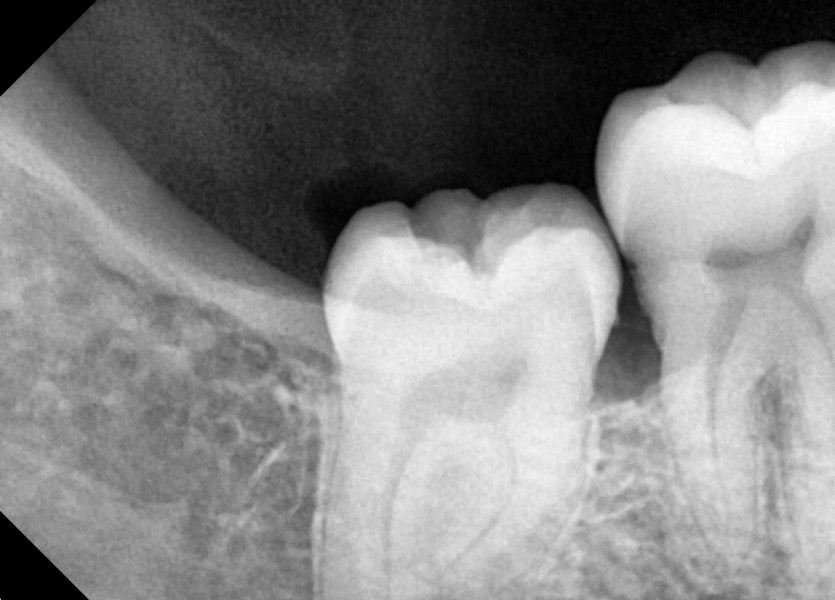

#48 사랑니 발치

구강 외과 전문의가 당일 발치했습니다.